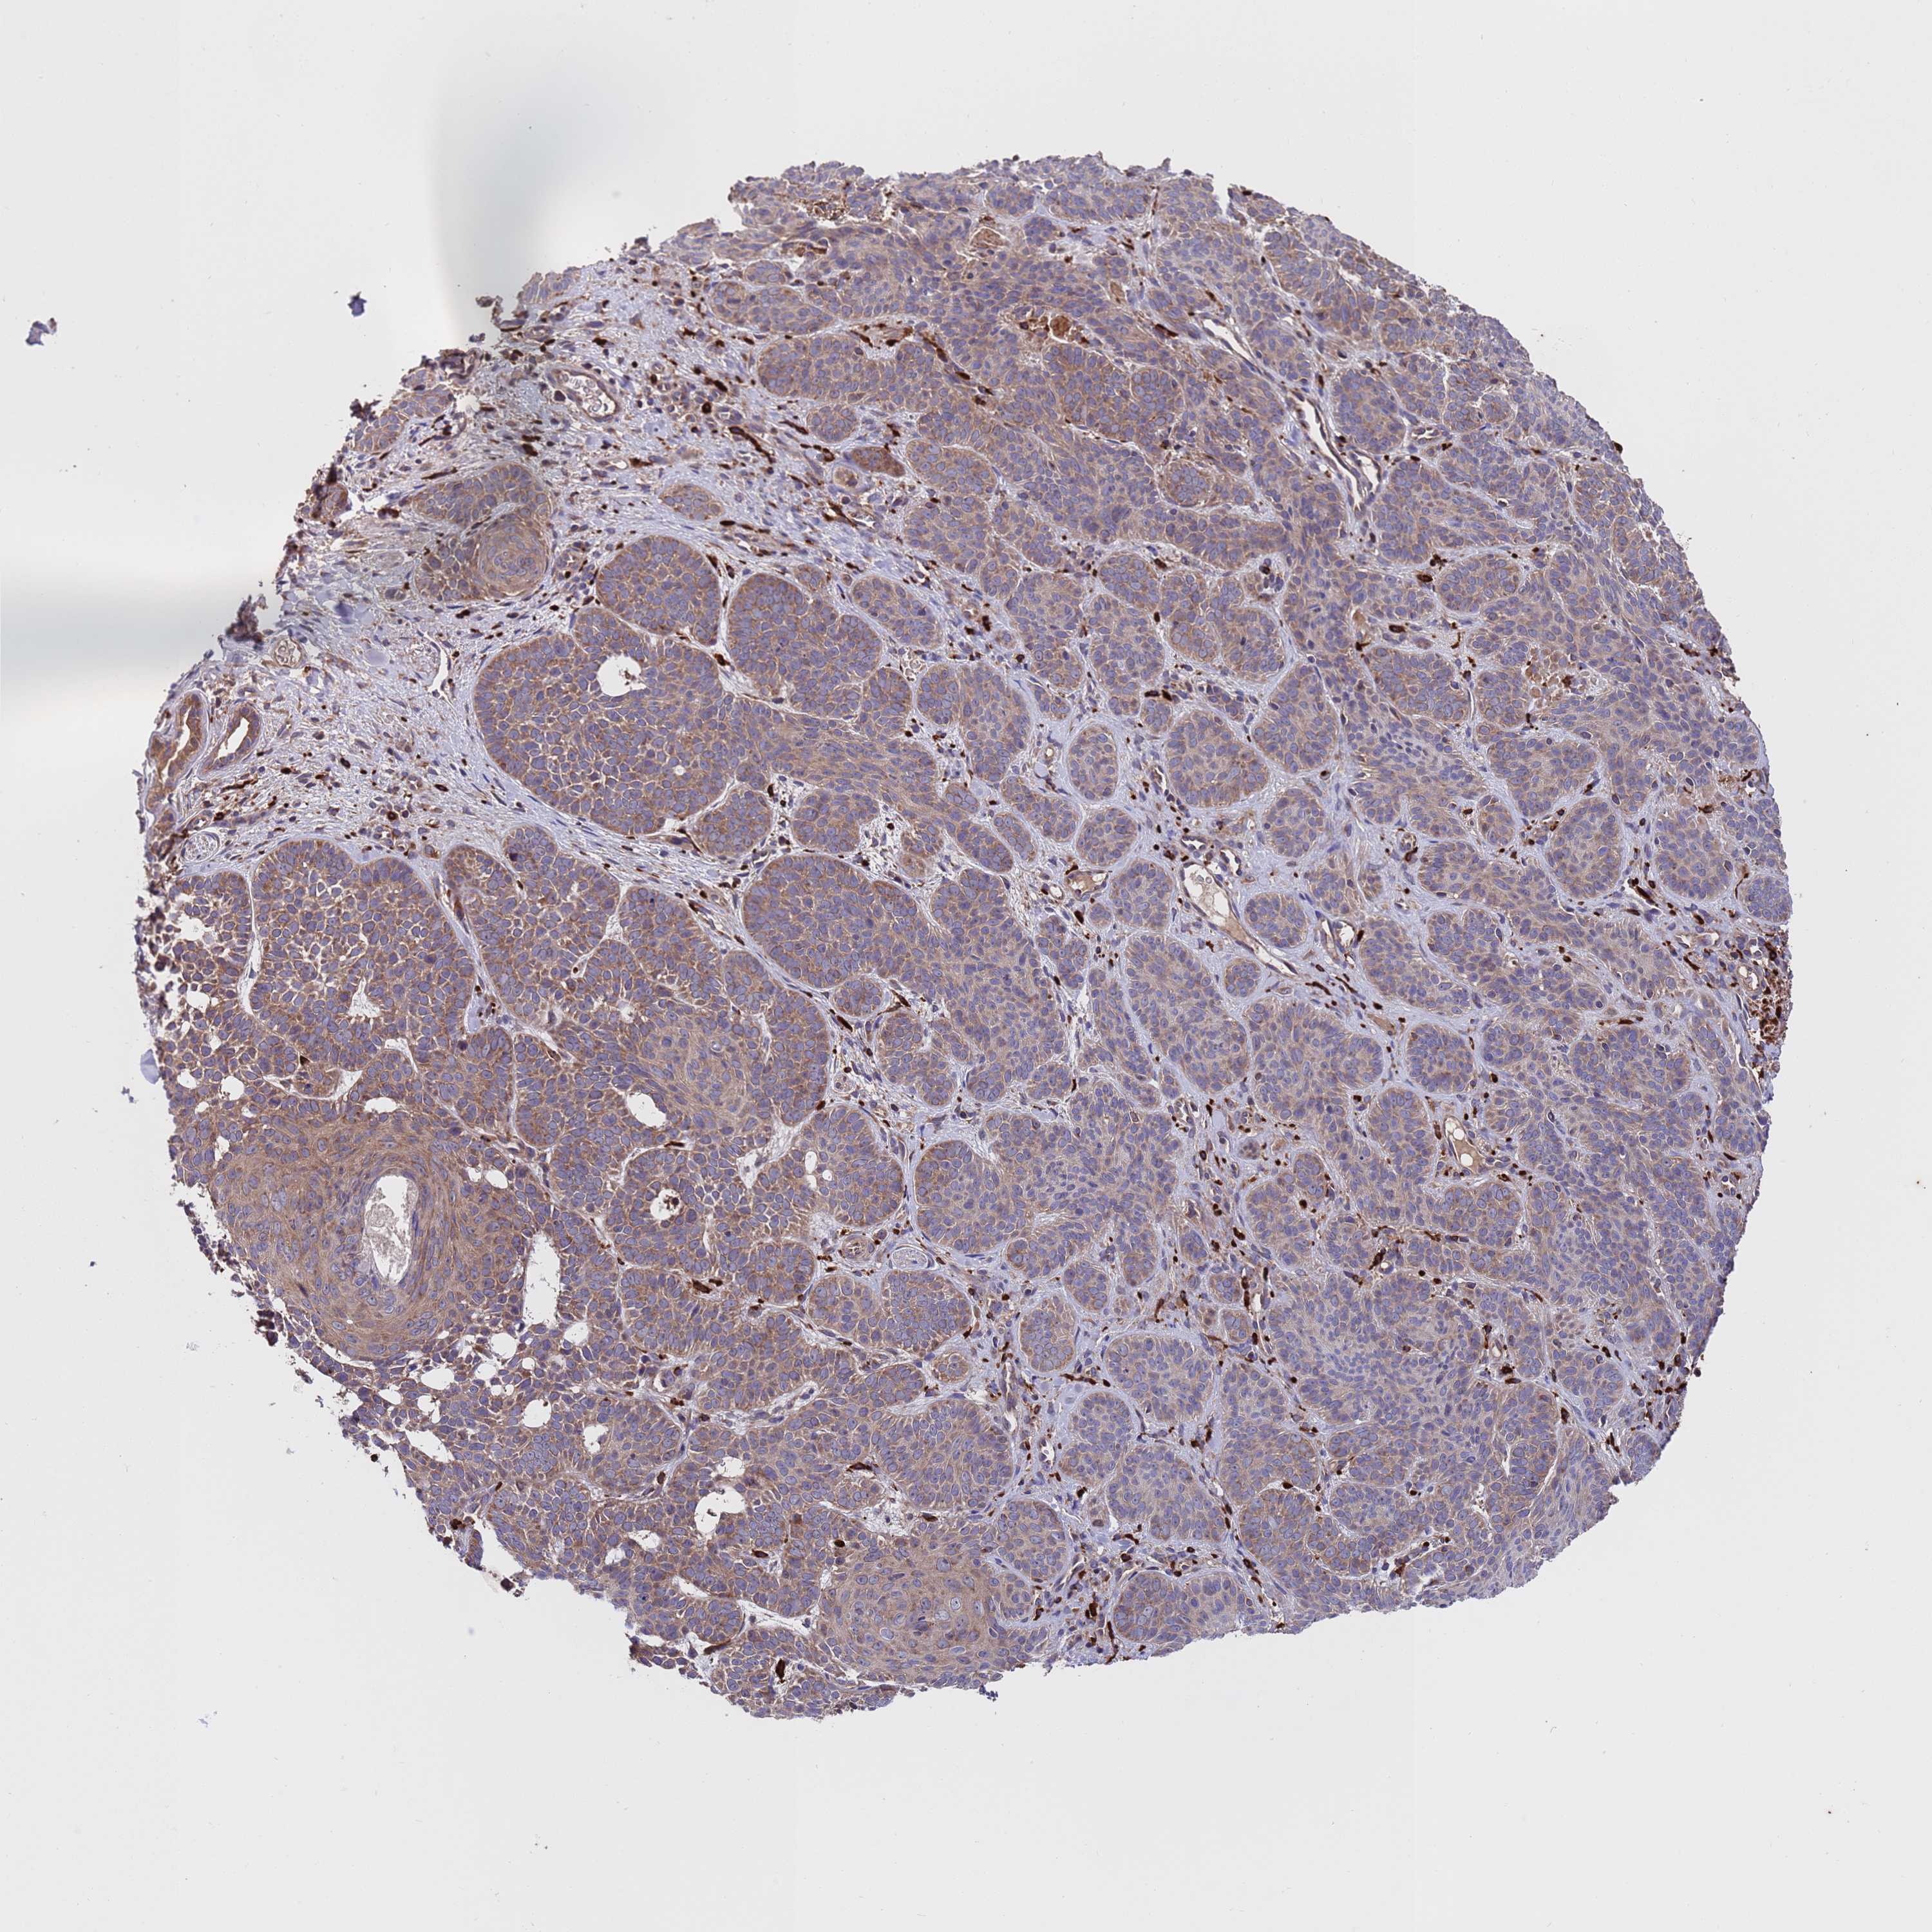

SKIN CANCER - Protein expressioni

A mouse-over function shows sample information and annotation data. Click on an image to view it in a full screen mode. Samples can be filtered based on level of antibody staining by selecting one or several of the following categories: high, medium, low and not detected. The assay and annotation is described here.

Each image is clickable and will lead to virtual microscopy that enables deeper exploration of all samples and also displays staining intensity scores, fraction scores and subcellular localization as well as patient and tissue information for each sample.

Antibody HPA046265

Staining

High

Medium

Low

Not detected

Intensity

Strong

Moderate

Weak

Negative

Quantity

>75%

75%-25%

<25%

None

Location

Nuclear

Cytoplasmic/membranous

Cytoplasmic/membranous,nuclear

Squamous cell carcinoma, NOS

Squamous cell carcinoma, metastatic, NOS

Basal cell carcinoma